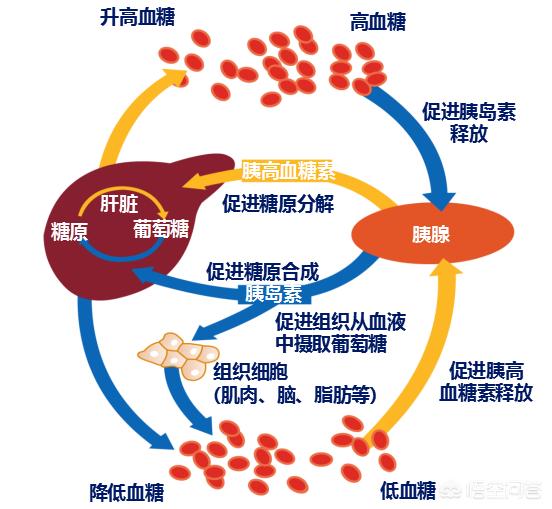

Le diabète est une maladie qui survient lorsque les cellules pancréatiques productrices d'insuline sont endommagées et meurent, produisant moins d'insuline pour transporter plus de sucre dans les cellules afin qu'il soit utilisé, ce qui entraîne une augmentation constante du taux de sucre dans le sang. Ce processus ne se produit pas en un court laps de temps, mais il s'agit plutôt d'une progression graduelle qui peut prendre des années ou plus.

La glycémie est la quantité de glucose dans le sang. Lorsque la glycémie est élevée à un certain niveau et que cet état persiste, le sang présente également un état hypertonique, de sorte qu'il existe une forte pression osmotique entre le sang et les tissus et cellules environnants, et que l'eau contenue dans les cellules continue de s'infiltrer dans la circulation sanguine, ce qui envoie un signal au cerveau concernant le manque d'eau, de sorte que le patient ressent la soif et a besoin de boire beaucoup d'eau.

De même, lorsque le sang passe par les reins, une grande quantité de sucre dans le sang, sous l'effet de la pression osmotique, entraîne une plus grande quantité d'eau dans l'urine, ce qui conduit à une augmentation de la quantité d'urine ; plus le sucre dans le sang est élevé, plus cet état se manifeste, ce qui explique la polyurie.

En raison du manque d'insuline de l'organisme, le sucre sanguin n'est pas pleinement utilisé, les cellules des tissus manquent d'énergie et se manifestent constamment au cerveau pour l'aider à signaler, le cerveau donnera des instructions pour manger plus afin d'augmenter la teneur en glucose du sang pour répondre aux besoins de l'organisme, le patient sera montré à manger pas assez à manger toujours vouloir manger les symptômes.

Dans des circonstances normales, outre le transport du glucose sanguin dans les cellules en vue de son utilisation, l'insuline convertit également l'excès de glucose sanguin et le stockage des graisses dans le foie et sous-cutané. Lorsque la sécrétion d'insuline est insuffisante dans une certaine mesure, même le transport du glucose sanguin dans les cellules ne peut satisfaire la demande, sans parler de la conversion du glucose sanguin en vue de son stockage, l'organisme doit également décomposer les graisses pour compenser le manque de glucose sanguin qui ne peut pas être utilisé, de sorte que le poids corporel diminue progressivement et que l'on devient de plus en plus mince. Le poids corporel diminue donc progressivement et l'organisme devient de plus en plus mince.